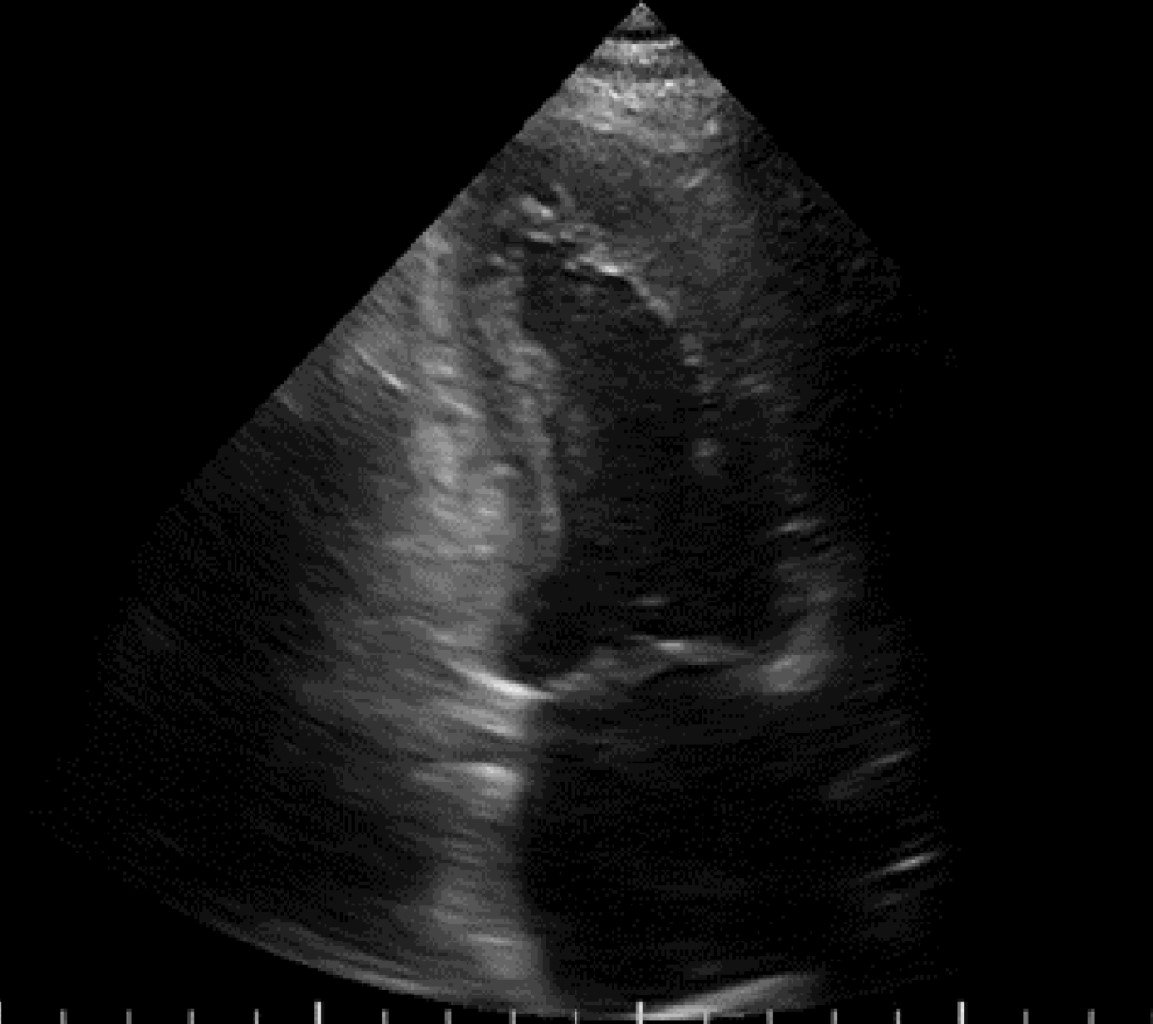

Ruptura cardiaca durante ecocardiograma de estrés con dobutamina como estratificación posterior a infarto agudo al miocardio

El ecocardiograma de estrés con dobutamina es ampliamente utilizado en la estratificación posterior a un infarto agudo al miocardio. Se han reportado complicaciones que pueden ser potencialmente mortales, siendo las arritmias ventriculares las más frecuentes. La ruptura cardiaca es una complicación rara, pero fatal. Se presenta el caso de un masculino de 68 años con un infarto inferior sin estrategia de reperfusión, el cual fue sometido a un ecocardiograma de estrés con dobutamina a los seis días del infarto. Durante la recuperación inicial el paciente presenta ruptura cardiaca por presencia de derrame pericárdico de aspecto hemático y disociación electro mecánica. Se realizó pericardiocentesis de urgencia, finalmente falleciendo el paciente. En la literatura se ha reportado el infarto inferior reciente y una zona discinética como las características de alto riesgo para presentarse. La selección adecuada del paciente, un ecocardiograma basal sin características de riesgo para ruptura y el tiempo de realización del estudio posterior al infarto puede disminuir la incidencia de esta complicación.

Figura 1